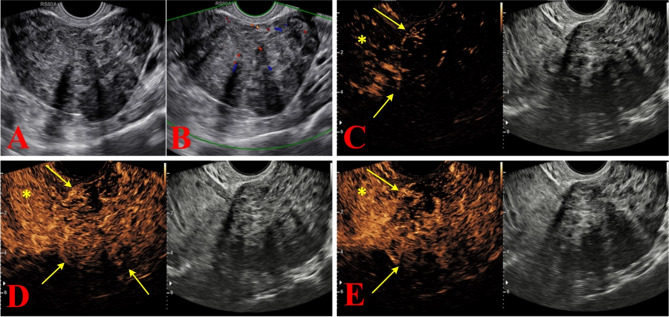

Methods: From January 2018 to August 2021 (the test group) and from September 2021 to September 2022 (the validation group), the data of patients classified as O-RADS US v2022 categories 2 to 5 who underwent adnexal ultrasound examinations were prospectively and continuously collected. In the test group, univariate and multivariate analyses were used to explore the relationship between age, body mass index (BMI), maximum diameter of the lesion, menopausal status, HE4, cancer antigen 125 (CA125), and the characteristics of CEUS and malignant lesions. Selecting independent influencing factors to construct diagnostic model, which was validated in the external validation group and compared with subjective evaluation.

Results: The test group included 563 patients (mean age, 48.7 ± 13.2), and the validation group included 246 patients (mean age, 47.6 ± 12.9). Univariate and multivariate analyses showed that enhancement time, enhancement intensity, dynamic changes, and HE4 were independent influencing factors for predicting adnexal malignant tumors. In the validation group, the sensitivities and specificities of O-RADS US v2022, O-RADS US v2022 + CEUS, O-RADS US v2022 + CEUS + HE4, and subjective assessment were 88.89% and 70.69%, 94.44% and 79.31%, 91.67% and 92.53%, and 93.09% and 89.66% respectively. In addition, the combined diagnostic performance of O-RADS US v2022, CEUS and HE4 (AUC = 0.980) was higher than that of O-RADS US v2022 alone (AUC = 0.876, P < 0.001) and the combination of O-RADS US v2022 + CEUS (AUC = 0.908, P < 0.001), and was comparable to the subjective evaluation (AUC = 0.963, P = 0.192).

Conclusions: The combined diagnostic model of O-RADS US v2022, CEUS and HE4 can improve the specificity of adnexal ultrasound diagnosis without sacrificing sensitivity, and it has high reliability.